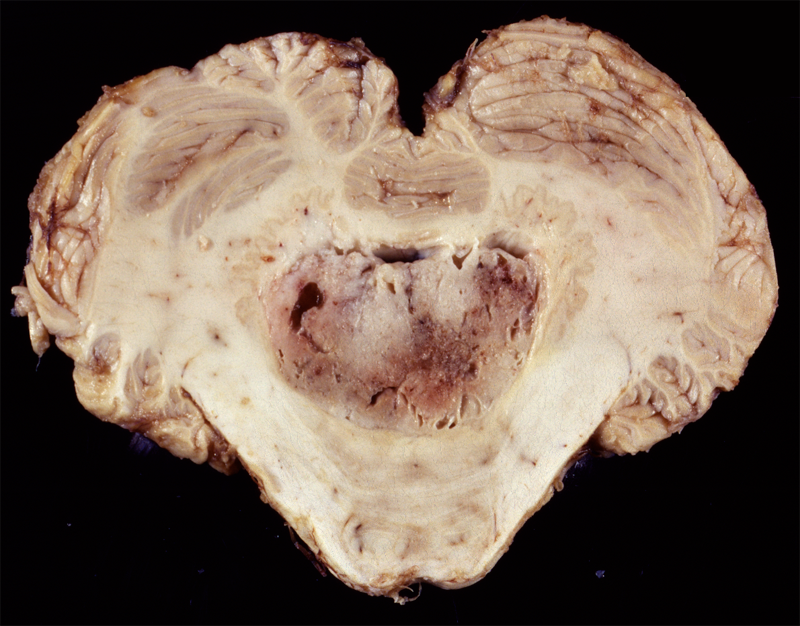

![]() Ependymoma of the 4th ventricle |

Ependymomas are predominantly tumors of children and adolescents. They arise most frequently in the fourth ventricle and cause hydrocephalus by blocking CSF flow. However, they may occur anywhere in relation to the ventricular system or central canal of the spinal cord and are the most common primary intra-axial tumors in the spinal cord and filum terminale. Ependymomas are well demarcated from the surrounding brain and grow in an exophytic fashion, protruding into and out of the fourth ventricle. Spinal ependymomas are circumscribed intra-axial masses. Some supratentorial ependymomas are exraventricular and may be cystic.